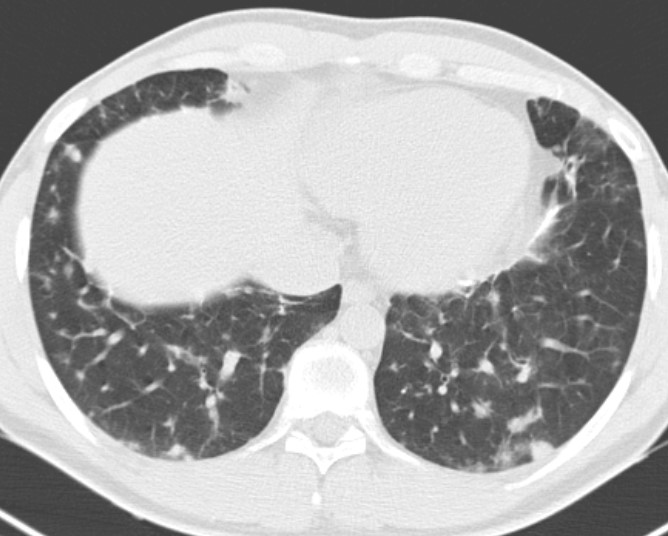

1. Рис. 1a. КТ органов гр. клетки у пациента с ОВИН. Figure 1a. Computer chest tomography of patient with common variable immunodeficiency | |